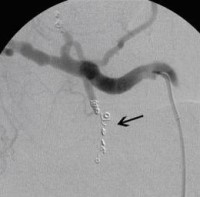

Postoperative abdominelle Blutungen bei chronischer Pankreatitis (Pfeile: Art. hepatica und Art. gastroduodenalis).

(Bild 1 von 5)

Postoperative abdominelle Blutungen bei chronischer Pankreatitis vor Embolisation der Art. gastroduodenalis mittels Metallspiralen (Coils)

(Bild 2 von 5)

Postoperative abdominelle Blutungen bei chronischer Pankreatitis nach Embolisation der Art. gastroduodenalis mittels Metallspiralen (Coils)

(Bild 3 von 5)